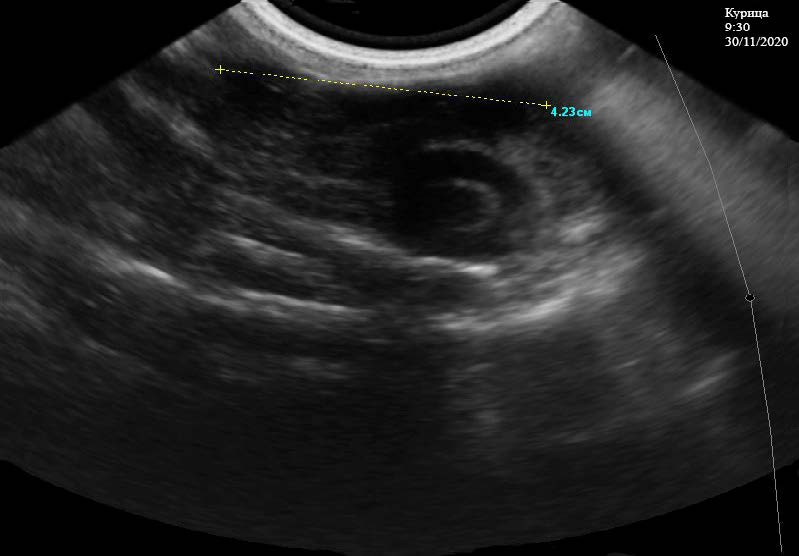

При ультразвуковом исследовании почек у курицы отмечается, что их границы ровные, четкие. Эхоструктура кортикального и мозгового слоев в срединной плоскости неоднородная, эхогенность паренхимы соответствует норме. Капсула не визуализируется. Отчетливо видно наличие более светлых и темных участков в паренхиме, что связано с фильтрацией минеральных веществ, содержащихся в крови. Мочеточники на всем протяжении не визуализируются. Общая длина почек составляет 4,70 см (рис. 1). Ультразвуковое исследование половых органов у курицы кросса Хайсекс белый проводилось в несколько этапов: Начало первого этапа проводили в 9:35 часов 30.11.2020 г. Отмечено наличие созревшего фолликула, который попадает в воронку. Выявляются локализованные объемные образования округлой формы – фолликулы, находящиеся на разных стадиях развития, размерами 0,96*0,99, 1,82*1,97, 0,57*0,70 см (рис. 2). Они имеют однородную эхогенность и эхоструктуру гиперэхоогенного характера, дающие слабую акустическую тень. Вокруг них визуализируется несколько мелких фолликулов, состояние границ между ними четкое просматривается, наличия артефактов не отмечено.

Рис. 1. Ультразвуковое исследование почек у курицы кросс «Хайсекс белый». 9:30 ч. 30.11.2020 г.